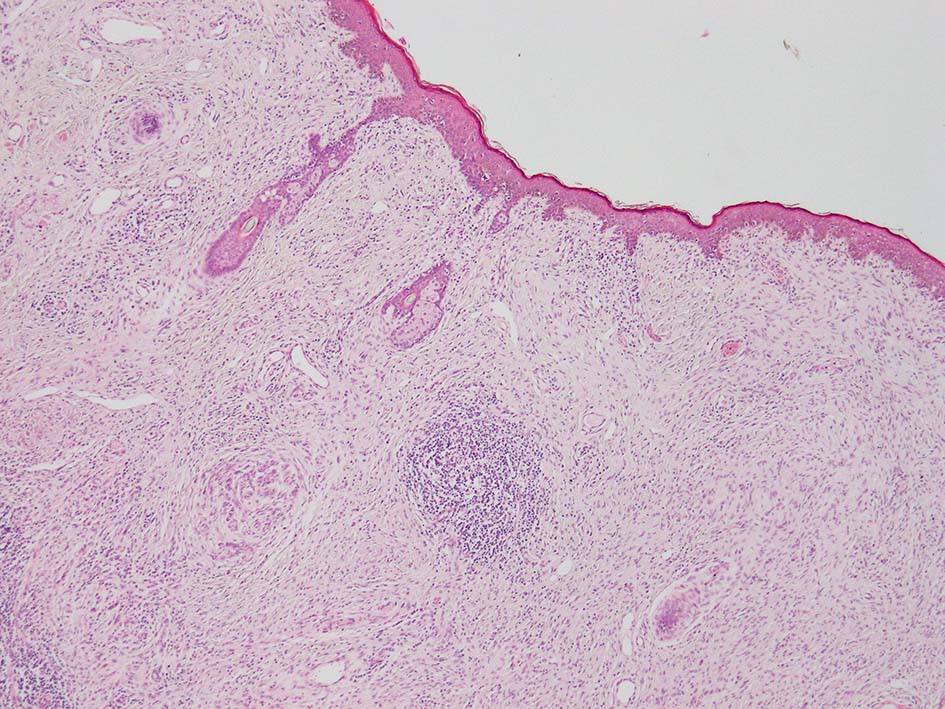

SPS244-Case01 右下眼瞼腫瘤 70歳代女性

初回皮膚生検組織

リンパ濾胞が細血管周囲に形成され, この部分に異型といえる細胞が増加している(S100+)